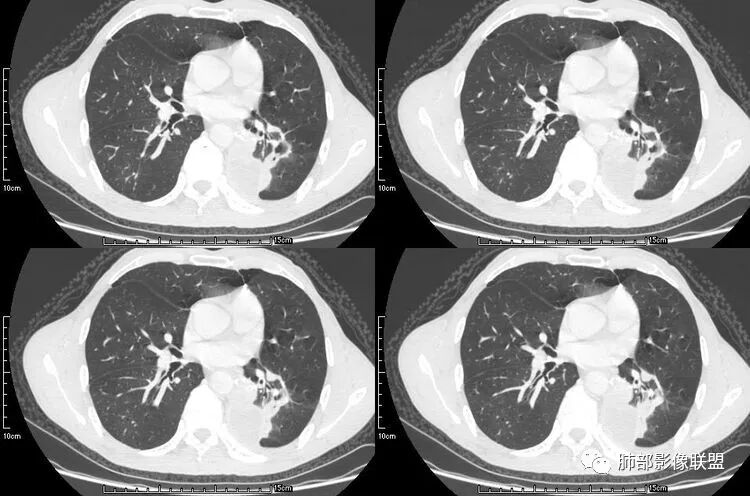

老年男性,咳嗽,咳痰带血2月,左下肺可见一团块影,深分叶,胸膜牵拉,可见坏死,坏死边界清,考虑恶性,双肺多发散在结节影,可见分叶,空洞,胸膜牵拉,考虑转移瘤;

患者老年男性,咳嗽、咳痰、痰中带血伴胸闷2月余。长期大量吸烟史。查肝肾功能、血糖、血脂、心肌酶、电解质、血沉、C反应蛋白、抗“O”、类风湿因子、抗核抗体谱无明显异常。肿瘤标志物提示NSE、CYFRA21-1稍升高。胸部CT:肺气肿背景,左肺下叶后基底段不规则肿块影,见支气管截断,内见大片状低密度区及部分血管影,增强轻度强化,远端空洞形成。双肺多发不规则实性结节影、见毛刺、胸膜牵拉及血管集束,结节内见空洞形成,部分可见血管影,多位于胸膜下。双肺见多发肺大泡。综合考虑左下肺恶性病变并双肺转移。鳞癌或淋巴瘤可能。鉴别血管炎性病变及真菌感染。

张延军:双肺多发结节,空洞影,后者洞壁厚薄不均匀,部分腔内丝丝落落,呈分叶征,边缘见毛刺影,病灶大部分位于胸膜下,与血管相连,右肺下叶前基底段结节近段支气管截断,远端见空腔。左肺下叶病灶密度不均,背段支气管壁增厚,管腔狭窄。考虑1.双肺下叶占位性病变伴肺内空洞性转移 2.多原发的占位 3.肉芽肿性血管炎代排。

本病例左肺下叶肿块,有深分叶、毛刺、胸膜牵拉凹陷、支气管截断及纵隔内淋巴结肿大等征象,都均支持病灶为恶性,如腺癌,而且叶间裂的多发结节也提示是腺癌来源可能大;双肺多发结节、肿块,大部分病灶有分叶、毛刺及胸膜凹陷的恶性征象,与原发肿瘤本身的性质有关,所以应该与左肺下叶肿块同源,而且双肺多发病灶内空洞也具有多样性;